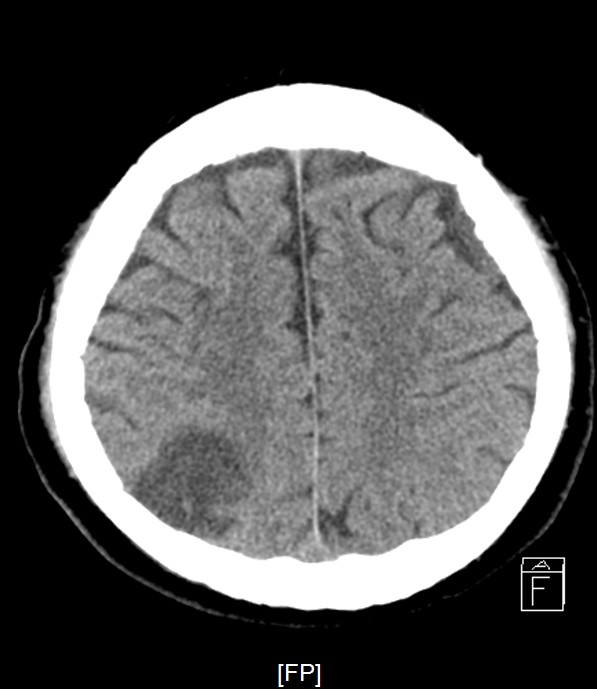

Staged PCI (Mar 6): One DES was placed in the LCX and one DCB in the LM–LCX segment. ECMO and IABP were successfully removed on March 8. Continuous renal replacement therapy was started for acute kidney injury. Brain CT showed watershed infarcts and a small subarachnoid hemorrhage, followed by gradual neurological recovery.